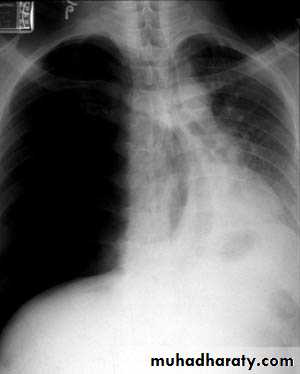

Chest X-ray;Shows the sharply defined edge of the deflated lung with complete translucency (no lung markings) between this and the chest wall. Chest X-rays also show the extent of any mediastinal displacement and give information regarding the presence or absence of pleural fluid and underlying pulmonary disease.